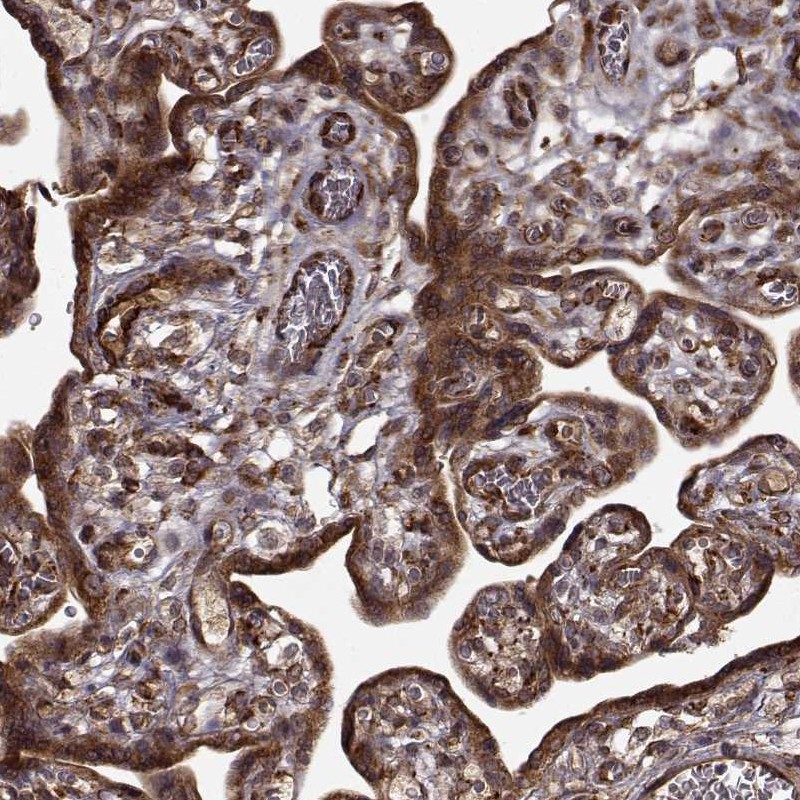

Immunohistochemical staining of human placenta shows strong cytoplasmic positivity in trophoblastic cells.